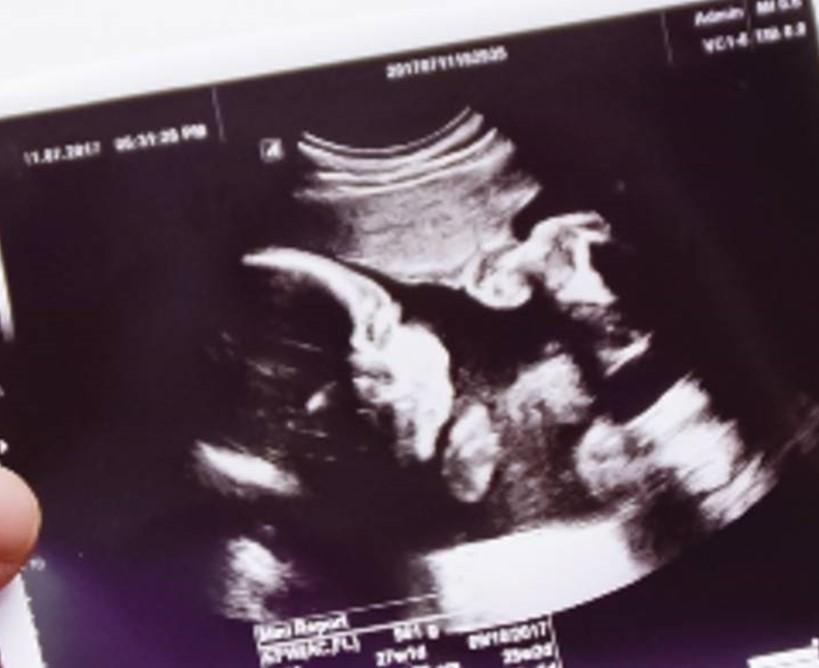

A partir de la semana 16 a la semana 18 (alrededor de los 4 meses de gestación) es cuando notarás cómo tu bebé empieza a realizar ligeras pataditas. Al llegar a la semana 30 (alrededor de los 7 meses), esta actividad será más recurrente.

La patada de un bebé en el vientre puede tener una fuerza de hasta 45 newtons, equivalente a 4.5 kilogramos de fuerza. Esto hará que con cada patadita, tu panza se estire en diferentes lugares.

En la fase final de embarazo, los bebés se dan vuelta para posicionar su cabecita en el canal de parto. Esto hace que las patadas sean más intensas y generen presión en las costillas.

Mamá podrá detectar la posición del feto dependiendo de sus movimientos. Si siente pataditas en la zona abdominal, es probable que su bebé se encuentre con la cabeza en el estómago; si patea por las costillas, es señal de que está de espaldas al vientre.